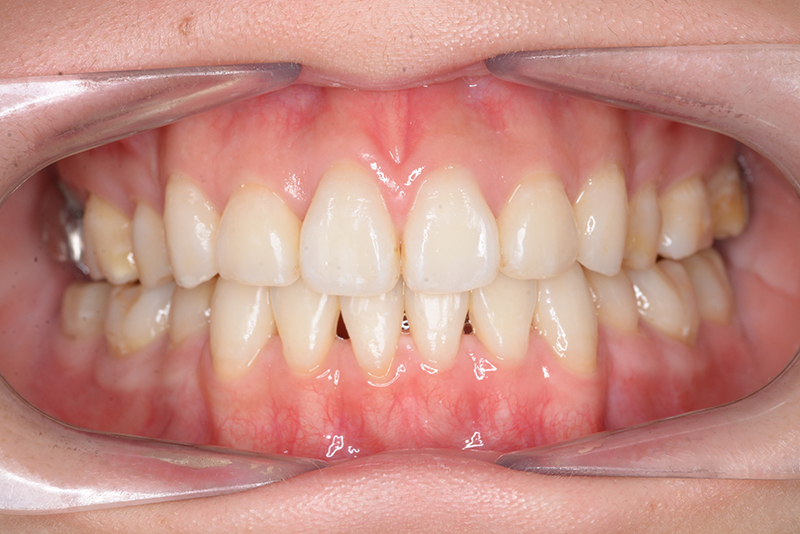

顔貌所見 正貌はほぼ左右対称。側貌はconvex type、Nasolabial Angleは小さく口唇は突出しており、閉唇時には口唇閉鎖不全が顕著に認められた。

口腔内所見 over jet 4.0mm、over bite 2.0mm、臼歯関係Ⅰ級、犬歯関係Ⅱ級で上顎前歯は唇側傾斜を呈しており、上下顎前突の様相を呈していた。

批評・予后 治療後、緊密な咬合の確立と共に大幅な切歯の後退によって主訴である口元の突出感と口唇閉鎖不全の改善が得られた。